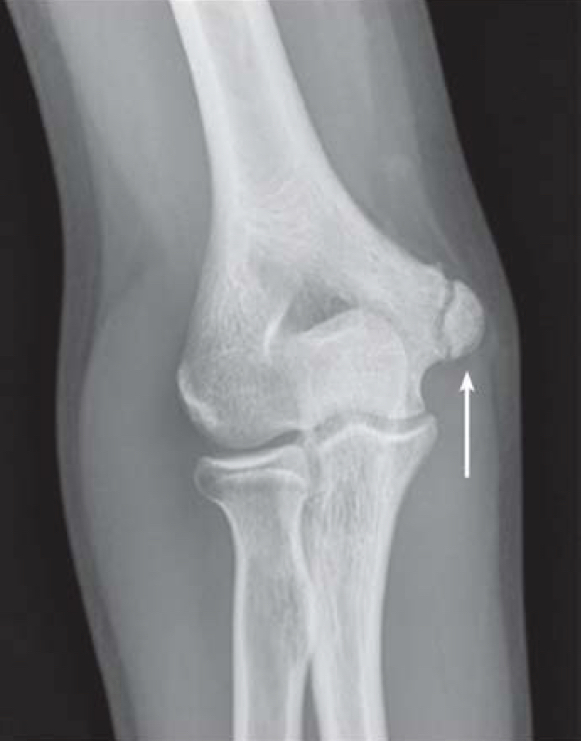

Wat is de naam van het afgebroken botdeel?

Epicondylus medialis